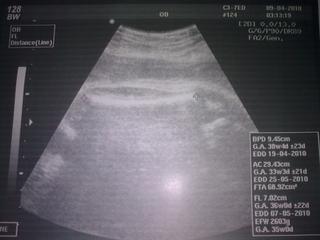

Ted jsem dorazila z pracáku, poradny a sociálk.y Poradna dopadla dobře, dělala stěry na streptokoka, brali odběry ... nechala jsem si udělat za 100,- UTZ, maličká je opět potvrzená jako ONA. Odhadem má 2600g, a máme větší hlavičku (myslím že to tady už řešila medan nebo kdo). Prý ji máme velkou jako strarosta 😀 Tak snad je vše ok. Napsala mi další Mg, že ho ještě týden mám brát a pak vysadit. V pondělí další poradna už s monitorem.